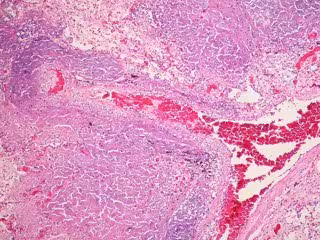

FLICKER/ PULMONARY PATHOLOGY

La tuberculosis es una infección causada por la Mycobacterium tuberculosis y que comúnmente afecta a los pulmones. A pesar de que es poco frecuente en Reino Unido debido a la vacunación con BCG, las mejoras en los niveles de vida y la introducción de un tratamiento antibiótico eficaz, ha aumentado desde finales de 1980 y sigue siendo un importante problema de salud global, responsable de casi de nueve millones de casos nuevos y 1,4 millones de muertes en 2011.